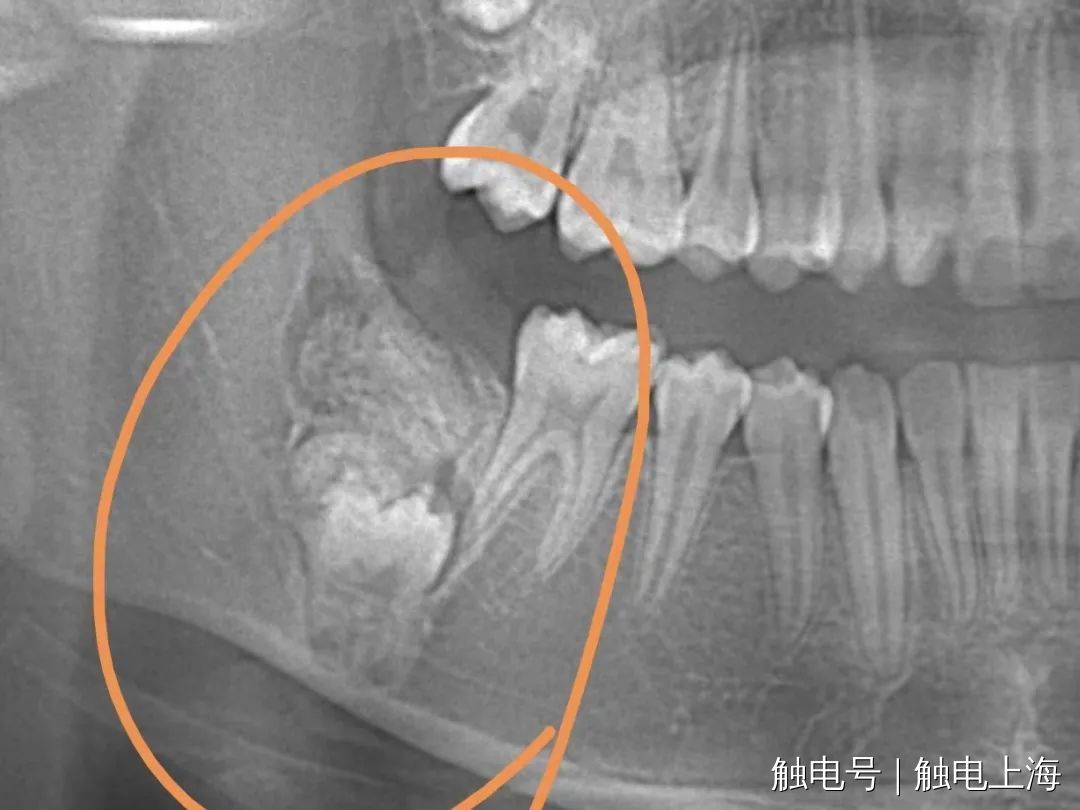

小雅右下颌骨内的瘤样病变

因为牙齿不整齐 , 父母带着12岁的小雅前往上海市儿童医院口腔科进行正畸治疗 , 拍片后发现小雅右下颌骨处存在着异样阴影 , 进一步诊疗发现 , 阴影是其右下颌骨内发生了瘤样病变 , 导致其右下第2恒磨牙在顶出来的途中遇到“埋伏” , 无法正常长出 。

口腔科主治医师段阿竹介绍说 , 牙瘤是牙源性肿瘤中的一种 , 生长于颌骨内 , 是以牙体组织杂乱排列成团或形成数量不等的畸形牙为特征的牙齿发育畸形 , 并非真性肿瘤 。 长出牙瘤的病因比较复杂 , 乳牙的慢性炎症、感染遗传因素、成牙本质细胞过度反应等都可能导致牙瘤发生 。 牙瘤可以引起恒牙迟萌、疼痛、颌骨膨隆、邻牙移位、松动 , 所以牙瘤患者通常伴随有缺牙现象 , 牙瘤严重者还可能导致骨缺损甚至引起骨折 。